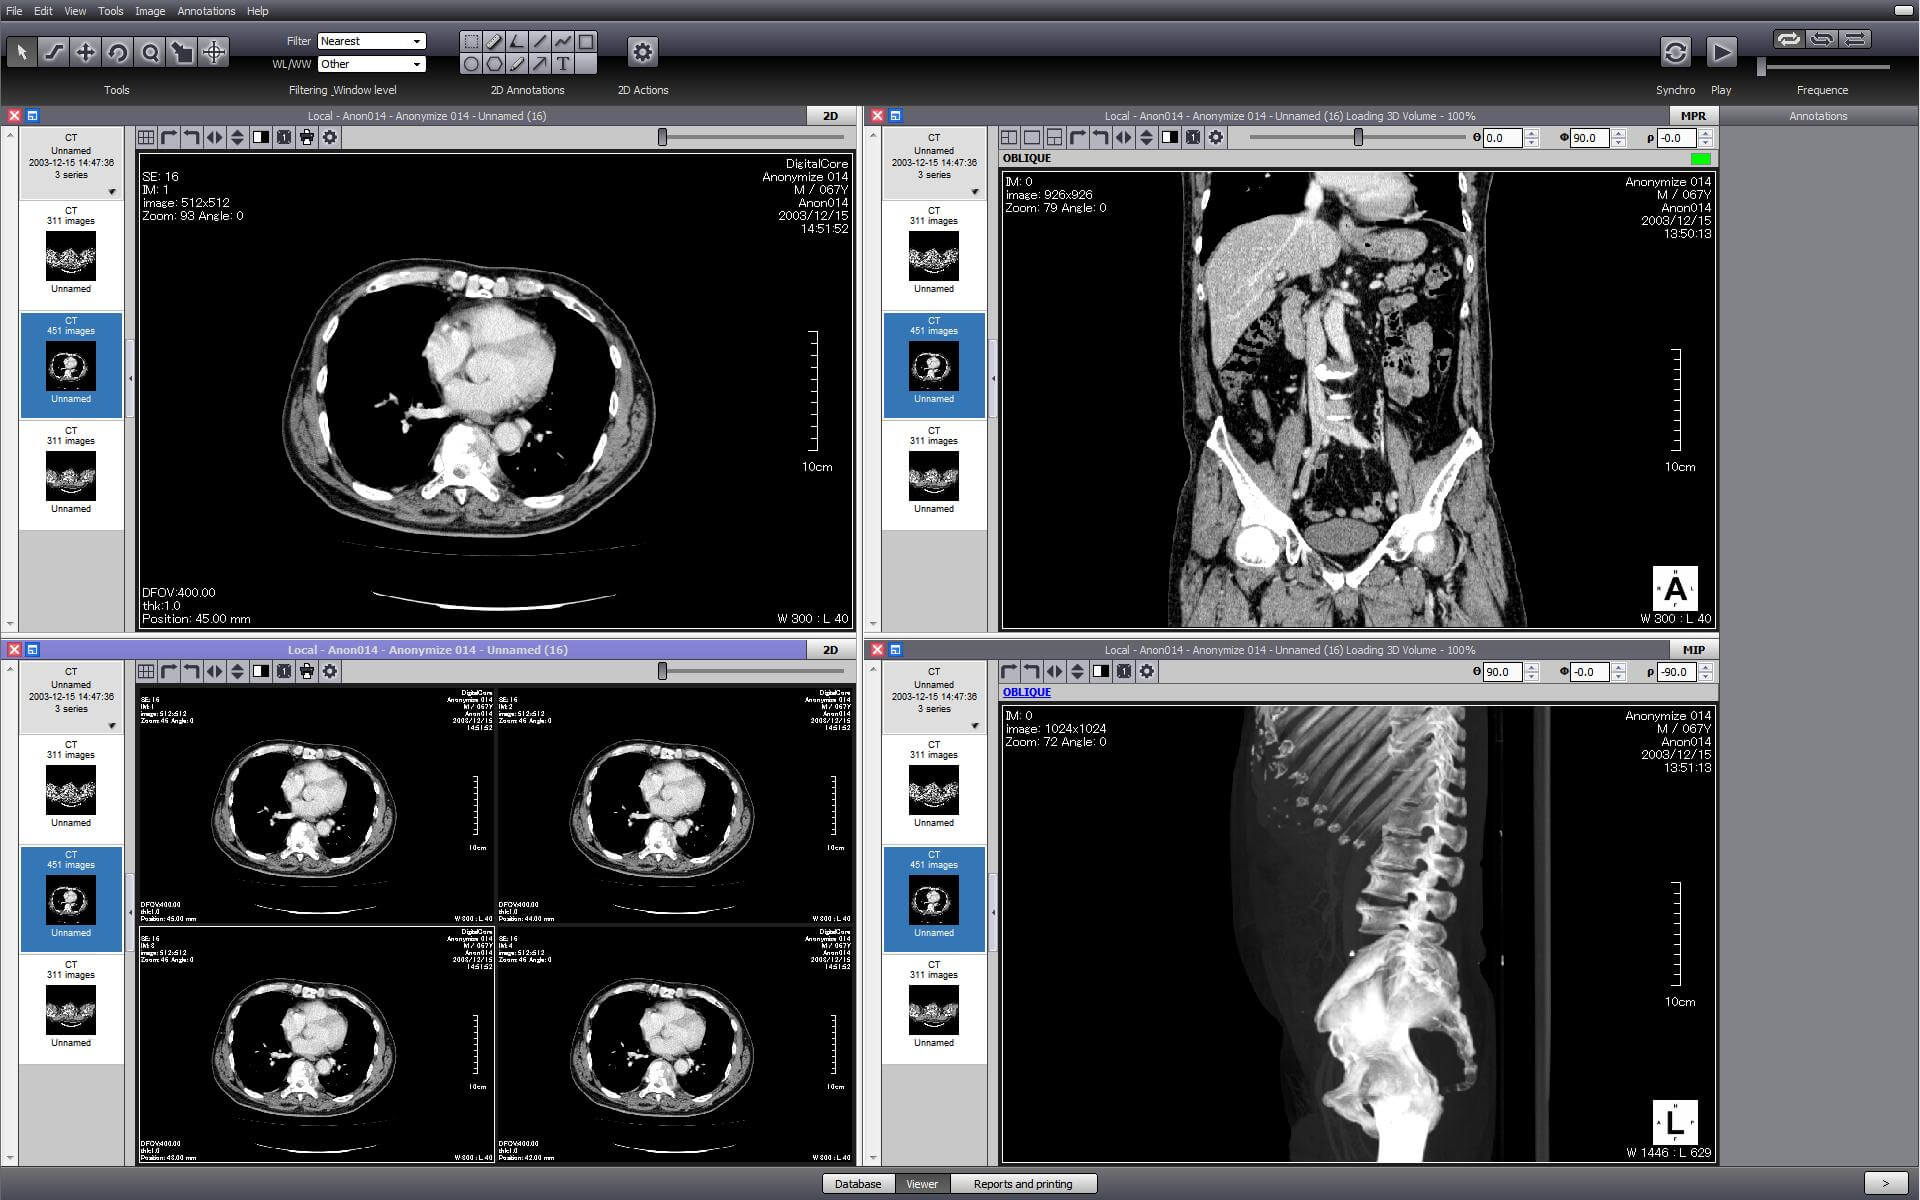

Лазерная камера для печати медицинских изображений на пленке стандарт dicom